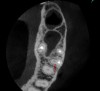

Finally, CBCT can help the clinician diagnose the cause of endodontic failures, especially when untreated canal anatomy is present (Figure 11).It can aid in determining whether a nonsurgical or surgical approach is needed. In addition, CBCT imaging is invaluable in surgical treatment planning, particularly if the roots of the tooth approach the maxillary sinus, mandibular canal, or mental foramen. For diagnosing root fractures or cracks, both horizontal and vertical, in this author's experience, root fractures can be seen on most CBCT scans if the crack has separated by at least 75 microns and most vertical root fractures are diagnosed by a narrow pattern of periradicular bone loss along the lateral aspect of a root.

Fig 11. 3D CBCT image of an untreated MB2 canal in tooth No. 14.

Figure 11